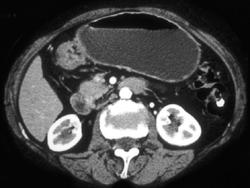

Gastric Adenocarcinoma